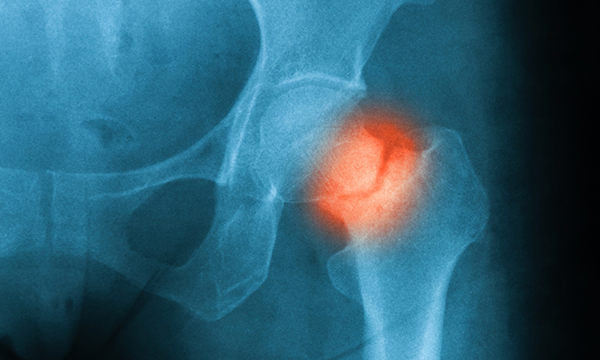

A small number of fractures go unnoticed in the emergency department, but the human and financial cost can be high, so nurses need to know the signs to look for